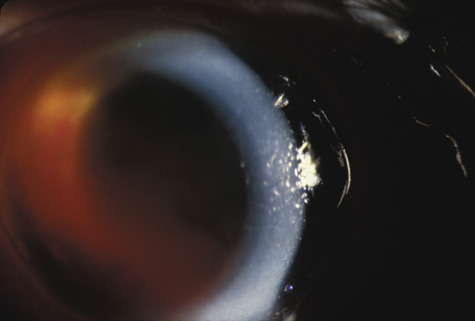

CHOROIDAL INJURIES Posterior choroidal ruptures are probably caused by anterior-posterior compression and equatorial expansion. The retina is relatively elastic, and the sclera is relatively tough. Both resist ruptures. Bruch's membrane, on the other hand, is inelastic and more prone to rupture. The overlying RPE and underlying choriocapillaris are also torn, but in most cases, the deep choroidal blood vessels remain intact (Fig. 19). Rupture of the choriocapillaris often results in subretinal hemorrhage. Patients with angioid streaks and other conditions known to be associated with a inelastic and fragile Bruch's membrane are especially vulnerable to choroidal rupture (Fig. 20).

Initially, a choroidal rupture may be obscured by a subretinal hemorrhage caused by tearing of the choriocapillaris. Later, after the blood has resorbed, a white curvilinear streak concentric to the optic disc is seen. Only rarely is a rupture oriented radially with respect to the optic disk. Most are temporal to the disc and single, although nasal and multiple ruptures can also occur (Fig. 21).

If the choroidal rupture is under the foveola or if an associated subretinal hemorrhage extends under the foveola, the visual prognosis is generally poor (Fig. 22); however, a recent study showed that even patients with foveal or multiple choroidal ruptures can regain good central vision after extended follow-up.86 If the rupture is elsewhere the prognosis is good because the overlying nerve fiber layer is almost never torn. Therefore, a rupture can be located between the disc and the macula and yet not affect the visual acuity (Fig. 21).